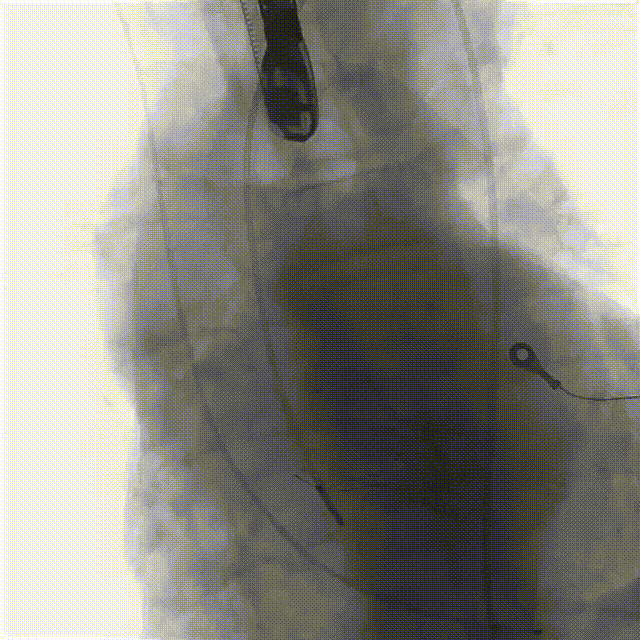

2.主动脉根部造影显示主动脉钙化严重、瓣叶活动度差,伴有轻度反流;

7.瓣膜释放至工作位后造影示左右冠灌注尚可,瓣膜形态尚可,决定予以释放

8.造影见明显反流影,瓣膜受限明显,决定予以球囊后扩

10.猪尾导管测压显示,平均跨瓣压差约12mmHg,造影示瓣膜定位尚可、开放良好,少量瓣周漏,患者血流动力学指标稳定,血压约100/70mmHg,升主动脉未见造影剂潴留或渗漏,标志手术成功。